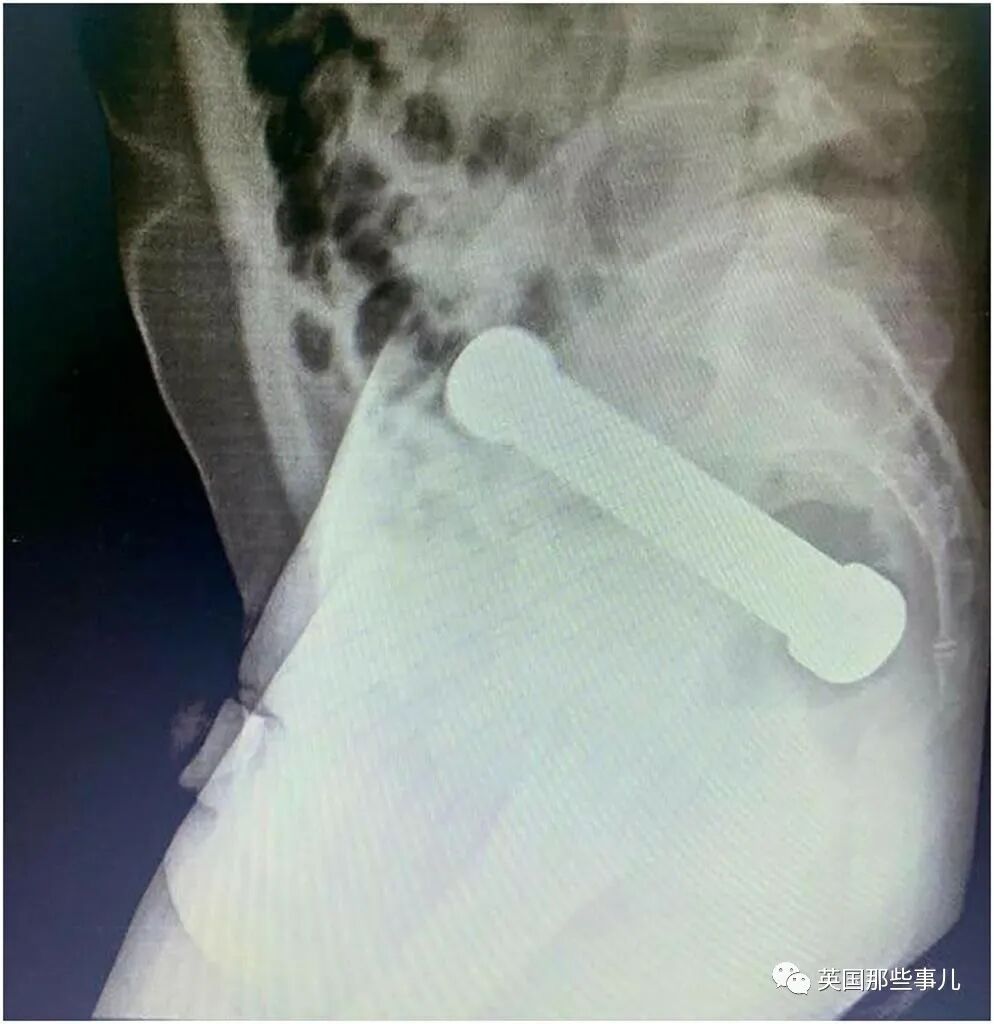

之前美国也有一位老哥,不慎将哑铃卡在体内,无法自行取出。

到急诊后有没主动说明情况,直到拍片子的时候,才真相大白。

医生表示,大多数因直肠异物而住院的患者,是年龄在20岁至40岁的男性。

其中最常见的原因,是出于“性满足”。

但许多病人会先自行尝试取出异物,等到多次失败后才会来到医院就诊。

这样一折腾,反而会耽误时间。

如果情况严重的话,可能会导致导致内伤和大便失禁。